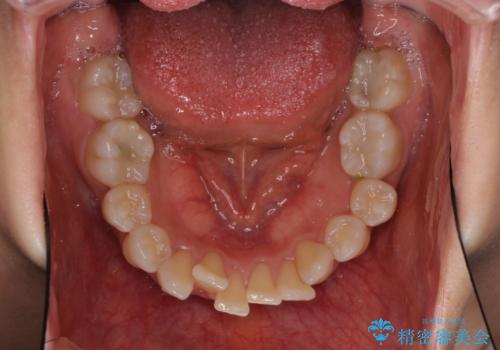

- 上の前歯の飛び出した感じと上下前歯のデコボコを気にして来院された患者様です。

叢生が強く、口元の突出感もあるため、上顎左右第一小臼歯4本を抜歯することとしました。

2年ほどインビザラインを使用しましたが、どうしても歯の移動がマウスピースに追随せず、全顎ワイヤー矯正へ切り替えました。